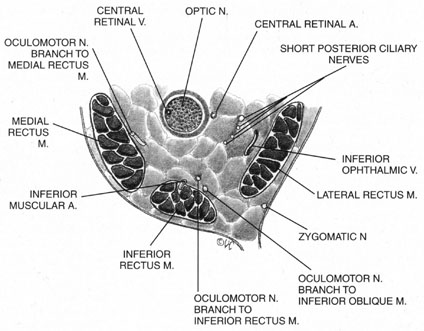

The ciliary ganglion is an irregular structure, measuring 1 mm by 2 mm, that lies just temporal to the optic nerve (Figs. 3 and 4), 7 to 10 mm from the orbital apex.47,51 In it the presynaptic parasympathetic fibers from the Edinger-Westphal nucleus synapse with the postsynaptic fibers that form the short ciliary nerves. Most of these fibers innervate the ciliary muscle, and the remaining 3% to 5% supply the iris sphincter. The ganglion also contains sensory branches of the nasociliary nerve and sympathetic fibers en route to the choroidal vasculature.

When attempting to provide akinesia, it should be kept in mind that the motor nerves enter the rectus muscles at the junction of their posterior and medial thirds, or more anteriorly.52 It is also important to remember that these fibers run both distally and proximally between the muscle fibers before they end at the myoneural junctions. A motor block may therefore be achieved at many points along their path. The oculomotor divisions may be blocked in the posterior orbit before their insertion into the rectus muscles, but it is necessary to keep in mind the proximity of the optic nerve, the ophthalmic vein, and the anterior muscular branches to the oculomotor branches in this region (see Fig. 3). Because the nerve and artery supplying the inferior oblique muscle insert more anteriorly, they are more vulnerable to needle trauma from peribulbar or retrobulbar blocks delivered along the floor of the orbit.48 The superior oblique muscle is innervated and receives its blood supply in the posterior orbit. Because it is relatively immobile in the superotemporal orbit, it is possible to injure this muscle with blocks in this area.